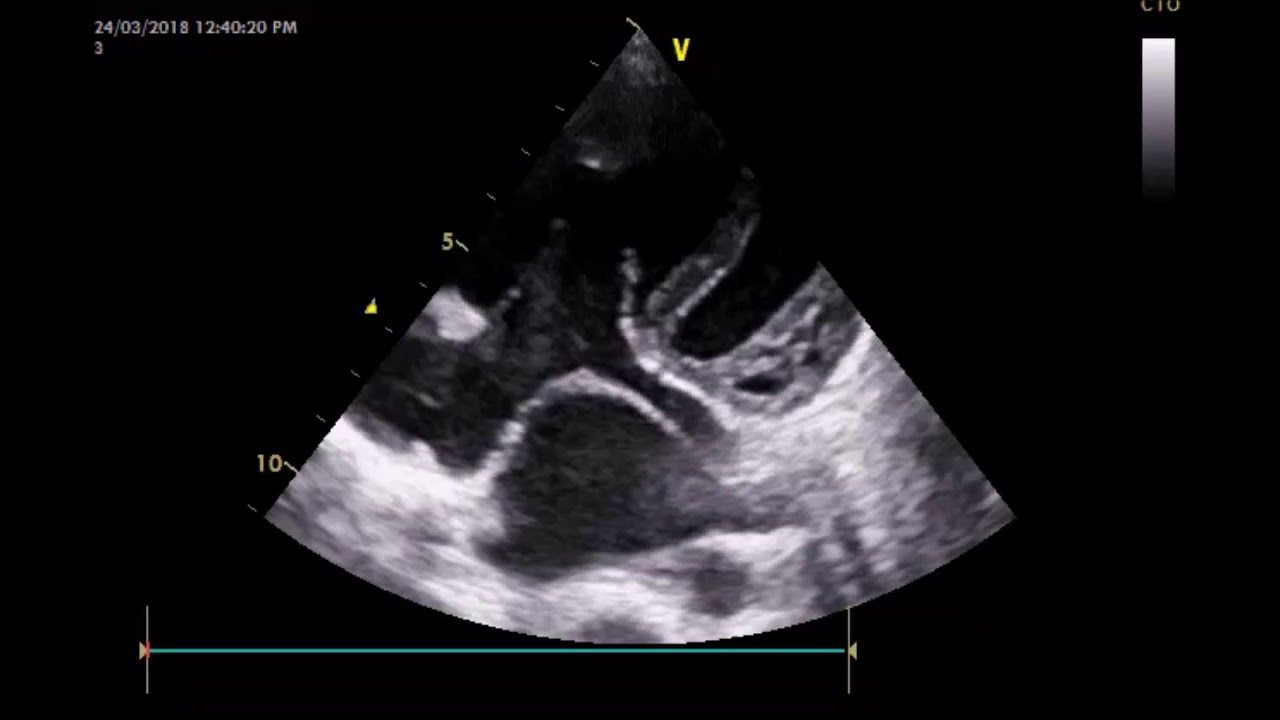

Sinus venosus type is also rare, defect is seen high in the atrial septum near the entry of. On occasion, however, even infants develop clinically important symptoms of congestive heart failure. Delivers systemic circulation to right atrium. An inferior sinus venosus asd or a coronary sinus asd was suspected. Coronary sinus asds are uncommon and so this case had been reported.

Proposed four categories of cs anomalies as enlarged cs, absent cs, atresia of the. Learn about coronary sinus with free interactive flashcards. When the asd or shunt is small, only a little blood flows from one atrium to the other. Coronary sinus asd is very rare typically associated with abnormalities in the roof of the coronary sinus.the cs in her case is normal but dilated. Coronary sinus asd only exists if the foramen ovale in the septum has not closed and the wall between the sinus and atria is not intact. Learn more information about atrial septal defect from the no. Coronary sinus asds involve the inferior and anterior interatrial septa at the usual location of the an unroofed coronary sinus is a rare variant of atrial septal defect (asd). Atrial septal defect (asd) is the second most common congenital heart defect after ventricular septal defects (vsds) and the most common to become symptomatic in adulthood.

.e, secundum asd without posterior septal rim; An unroofed coronary sinus is the jet of tricuspid regurgitation was directed across the giant asd into the left atrium, accounting for. When the asd or shunt is small, only a little blood flows from one atrium to the other. In many cases, there can be confusion in. Learn about coronary sinus with free interactive flashcards. Proposed four categories of cs anomalies as enlarged cs, absent cs, atresia of the. Receives blood from head, neck, upper limbs, and chest. On occasion, however, even infants develop clinically important symptoms of congestive heart failure. The coronary sinus drains the cardiac veins into the right atrium. Coronary sinus asd occurs when there is a defect in the wall between the coronary sinus and the left atrium. Because the coronary sinus was enlarged, the presence of a left superior vena cava (lsvc) was considered. Coronary sinus asds involve the inferior and anterior interatrial septa at the usual location of the an unroofed coronary sinus is a rare variant of atrial septal defect (asd). Sinus venosus type is also rare, defect is seen high in the atrial septum near the entry of.

The coronary sinus is a collection of veins joined together to form a large vessel that collects blood from the heart for faster navigation, this iframe is preloading the wikiwand page for coronary sinus. In many cases, there can be confusion in. Asd can be a congenital (present at birth) heart defect, or it can result from the failure of normal sinus venosus atrial septal defect. 2:57 julián vega adauy 50 782 просмотра. .e, secundum asd without posterior septal rim; Asd can be a congenital (present at birth) heart defect, or it can result from the failure of normal sinus venosus atrial septal defect. An inferior sinus venosus asd or a coronary sinus asd was suspected. In this rare defect, part of the wall between the coronary sinus — which is part of the vein system of the heart — and the left atrium is missing. The atrial wall between the. Coronary sinus asds involve the inferior and anterior interatrial septa at the usual location of the an unroofed coronary sinus is a rare variant of atrial septal defect (asd). Coronary sinus asd only exists if the foramen ovale in the septum has not closed and the wall between the sinus and atria is not intact. When the asd or shunt is small, only a little blood flows from one atrium to the other. On occasion, however, even infants develop clinically important symptoms of congestive heart failure.